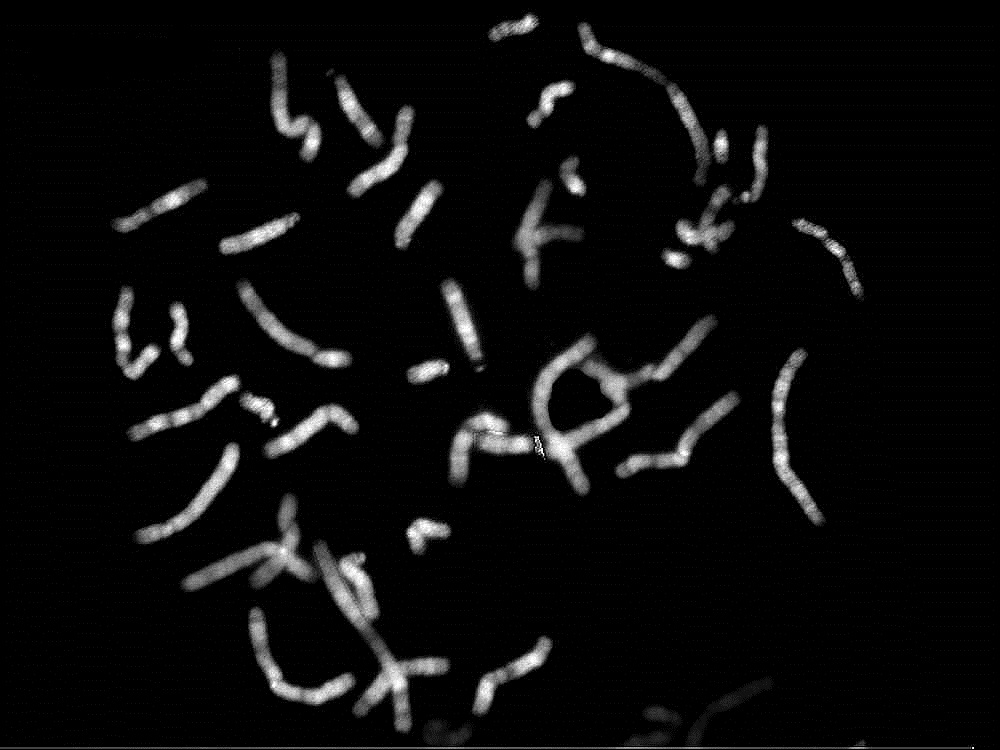

1. BANDEADO DE GIEMSA

Annotations:

• Bandeado G.

• Es una técnica de identificación de anomalías genéticas en la que las preparaciones cromosómicas son teñidas con Giemsa para revelar patrones únicos para cada cromosoma.